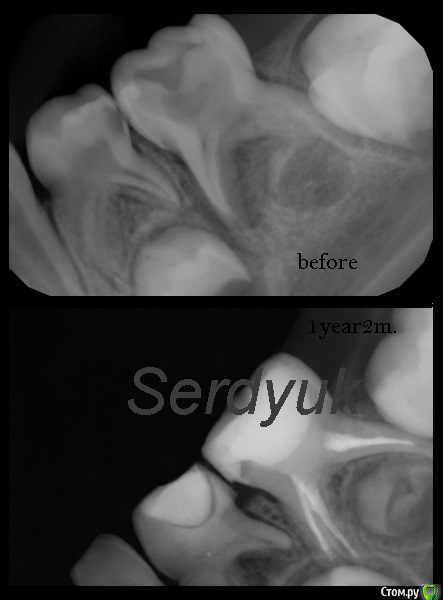

Джима Опубликовано 24 октября, 2016 Поделиться Опубликовано 24 октября, 2016 Чойто я тут должна вдруг? Ребят, это зачаток под 8.5. Кota, полностью поддерживаю. Почитайте сроки закладки, что ли. вот, раньше показывала:кажись, 5 лет, второй снимок больше года спустя Ссылка на комментарий

crown Опубликовано 24 октября, 2016 Поделиться Опубликовано 24 октября, 2016 Чойто я тут должна вдруг? Ребят, это зачаток под 8.5. Кota, полностью поддерживаю. Почитайте сроки закладки, что ли. вот, раньше показывала:7.5.jpgкажись, 5 лет, второй снимок больше года спустяНу надо же вас как то привлечь. На вашем снимке сразу видно что что то назревает) а тут просто пятно черное. В 3 года пишут что закладывается, поэтому и возникли сомнения Ссылка на комментарий

Джима Опубликовано 24 октября, 2016 Поделиться Опубликовано 24 октября, 2016 (изменено) так мой снимок постарше, кончик бугра минерализуется уже. у автора, по-моему, тоже видно контуры зачатка.а вот снимок 7.5 выглядит как раз таки так, как будто зачаток был и погиб. Изменено 24 октября, 2016 пользователем Джима Ссылка на комментарий

Stom22 Опубликовано 26 октября, 2016 Поделиться Опубликовано 26 октября, 2016 (изменено) Извиняюсь за дезинформацию. Во внутриутробном периоде, начиная с 5 месяцев, начинается закладка зачатков постоянных зубов и продолжается она до 5 лет. Во внутриутробном периоде закладываются 16 постоянных зубов (все резцы, клыки и первые большие коренные зубы). Все остальные после рождения. Самая поздняя закладка постоянных зубов происходит в 5 лет и это закладка третьего большого коренного зуба. Закладка второго большого коренного зуба происходит в 2,5 года.Ну и зачаток второго малого коренного зуба возникает в 2 года, в 2,5 года оказываются два очага минерализации. Тут же ребёнку 4 года и очагов минерализации мы не видим. Всё таки склоняюсь к тому, что зачатка нет. Но это покажет время. У родителей бы спросила насчёт позднего прорезывания молочных зубов, если имело место такое, то не исключена и поздняя закладка и прорезывание постоянных, но судя по возрасту и снимку всё же остаюсь при своём мнении. Изменено 26 октября, 2016 пользователем Stom22 Ссылка на комментарий

Джима Опубликовано 26 октября, 2016 Поделиться Опубликовано 26 октября, 2016 Stom22. Это зачаток. Время рассудит, конечно, но это зачаток. 99%Искала для вас панорамки, вот нашла: http://pdnr.ru/a4679.html, там есть панорама ребёнка пяти лет. По-моему, на снимке у автора даже минерализацию видно слегка. Переделать бы снимок по-человечески. Ссылка на комментарий